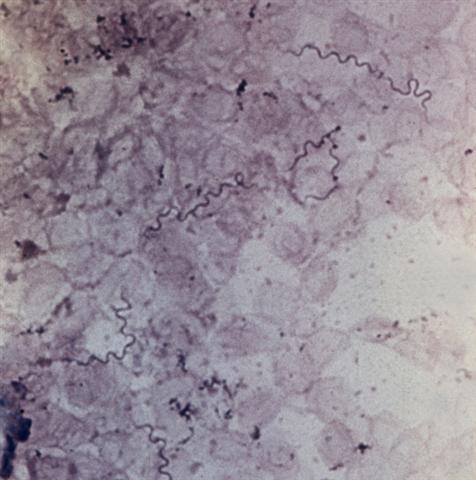

Рис. 2. Многочисленные спирохеты (Borrella persica) в мазке из крови больного клещевым возвратным тифом; окраска по Романовскому — Гимзе; х 800.